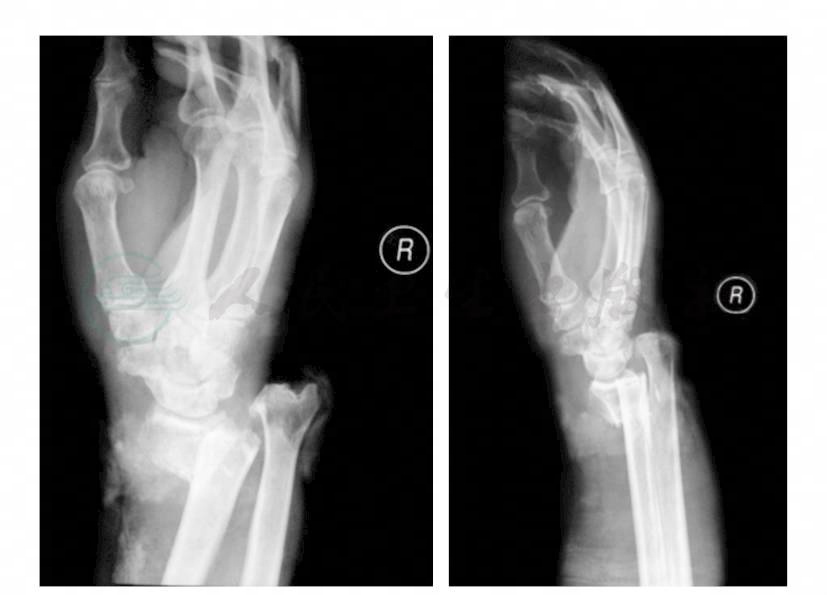

麻醉成功后患者取仰卧位,右上肢外展,右上臂绑止血带。肥皂水清洗伤口周缘皮肤,生理盐水、过氧化氢、苯扎溴铵反复冲洗伤口。碘附消毒、铺单。止血带充气220mmHg,各创口扩创,切除碎裂的污染组织,修剪皮缘。探查桡动脉、尺动脉、正中神经、尺神经,均完整无明显损伤。尺侧腕屈肌部分断裂,旋前方肌破坏严重,将血运差的肌肉组织清除。清创后用过氧化氢、生理盐水、稀释的碘附反复冲洗。更换器械、手套,重新铺单。桡骨远端干骺端粉碎性骨折,骨质缺损严重,无法解剖复位。修整断端,还纳尺骨头,予以复位。一枚克氏针固定桡骨断端,另两枚克氏针固定下尺桡关节。跨腕关节于第二掌骨干和桡骨干放置外固定架,固定腕关节于功能位。透视见骨折功能复位(图2)。尺侧和桡背侧伤口分别放置VSD负压引流海绵,边缘与皮缘缝合数针固定,贴膜封闭,予以持续负压吸引。术后患者安全返回病房。

图2 术后腕关节正侧位X线片